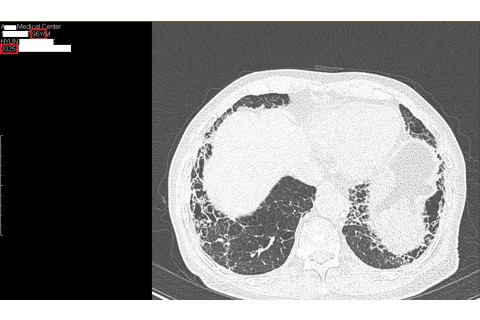

숨케어한의원에서는 전화예약을 받고 있습니다. 내원시 엑스레이, CT사진, 폐기능검사지를 가지고 오시면 자세한 상담이 가능합니다.